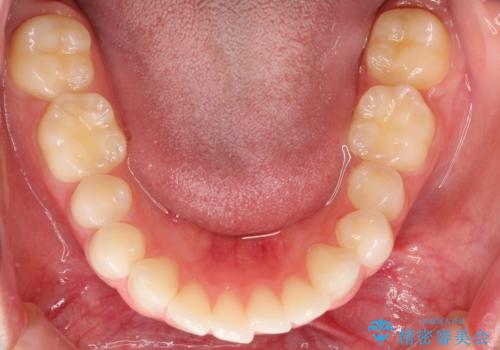

出っ歯の矯正治療 歯を抜かずにインビザラインで

- インビザラインで出っ歯を治したいとの希望がありました。

上顎の歯を全体的に後方に移動させて前歯を引っ込める計画としました。